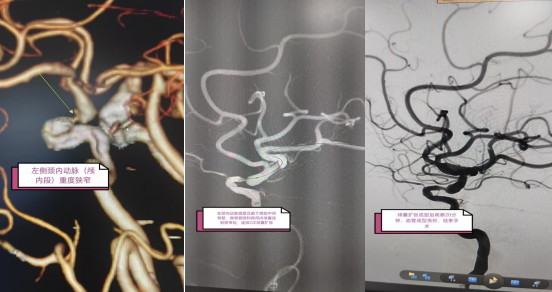

患者因头晕、行走不稳、恶心呕吐等症状,到彭州市人民医院神经内科接受治疗。完善头颈部CT血管成像检查后,明确为左侧颈内动脉颅内段重度狭窄,双侧颈内动脉极度迂曲,手术难度极大。面对挑战,神经内科卒中中心团队迎难而上,决定为患者行左侧颈内动脉成型术:左侧颈内动脉狭窄球囊扩张+支架置入术。

经过充分的术前准备,神经内科苟重季主任带领介入医疗组长卓开全主治医师、付丽主治医师与麻醉科、导管室紧密配合,凭借精湛技术克服颈内动脉迂曲难题,顺利将球囊送达狭窄处并完成两次扩张,球囊扩张成型后观察20分钟,血管成型良好,狭窄处血流明显改善,远端血管显影正常,未见闭塞血管。麻醉复苏后见患者言语清晰,双侧肢体活动正常,手术取得圆满成功。